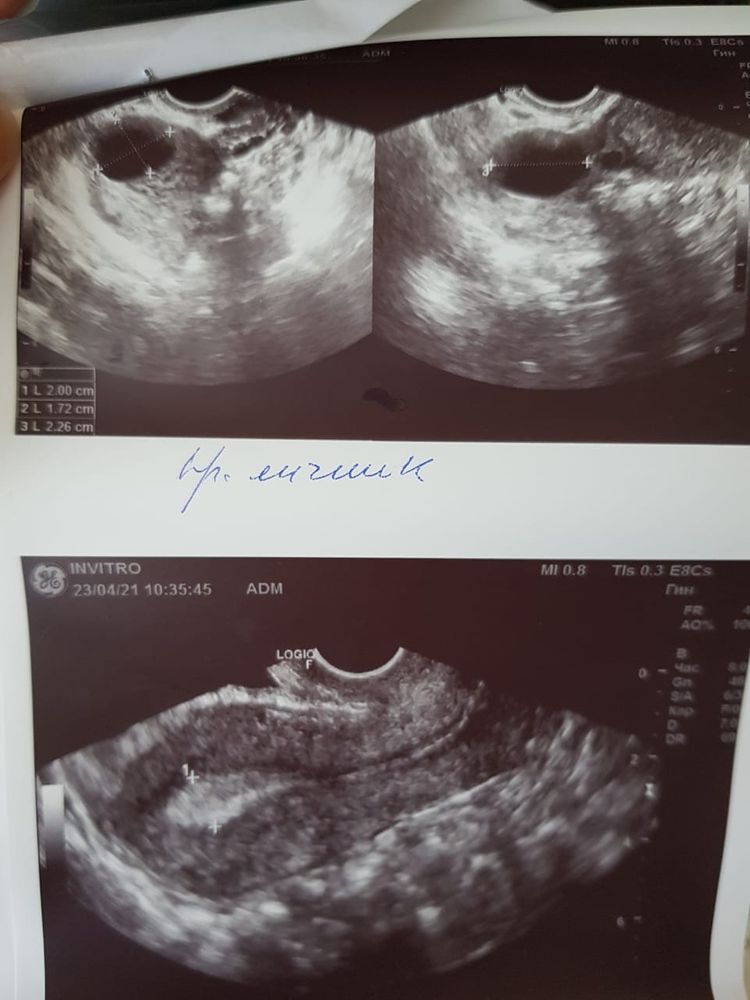

ФолликулометрияВ правом яичнике намерили ДФ 20мм (20x17x23) и ЖТ 14x11x17 с кровотоком.